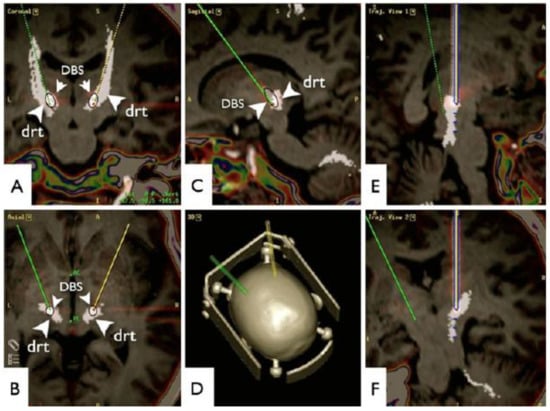

- Coenen, V.A.; Allert, N.; Madler, B. A role of diffusion tensor imaging fiber tracking in deep brain stimulation surgery: DBS of the dentato-rubro-thalamic tract (DRT) for the treatment of therapy-refractory tremor. Acta Neurochir. (Wien) 2011, 153, 1579–1585; discussion 1585. [Google Scholar] [CrossRef] [PubMed]

- Coenen, V.A.; Allert, N.; Paus, S.; Kronenburger, M.; Urbach, H.; Madler, B. Modulation of the cerebello-thalamo-cortical network in thalamic deep brain stimulation for tremor: A diffusion tensor imaging study. Neurosurgery 2014, 75, 657–669; discussion 669–670. [Google Scholar] [CrossRef] [PubMed]

- O’Halloran, R.L.; Chartrain, A.G.; Rasouli, J.J.; Ramdhani, R.A.; Kopell, B.H. Case Study of Image-Guided Deep Brain Stimulation: Magnetic Resonance Imaging-Based White Matter Tractography Shows Differences in Responders and Nonresponders. World Neurosurg. 2016, 96, 613.e9–613.e16. [Google Scholar] [CrossRef] [PubMed]

- Sajonz, B.E.; Amtage, F.; Reinacher, P.C.; Jenkner, C.; Piroth, T.; Kätzler, J.; Urbach, H.; Coenen, V.A. Deep Brain Stimulation for Tremor Tractographic Versus Traditional (DISTINCT): Study Protocol of a Randomized Controlled Feasibility Trial. JMIR Res. Protoc. 2016, 5, e244. [Google Scholar] [CrossRef] [PubMed]